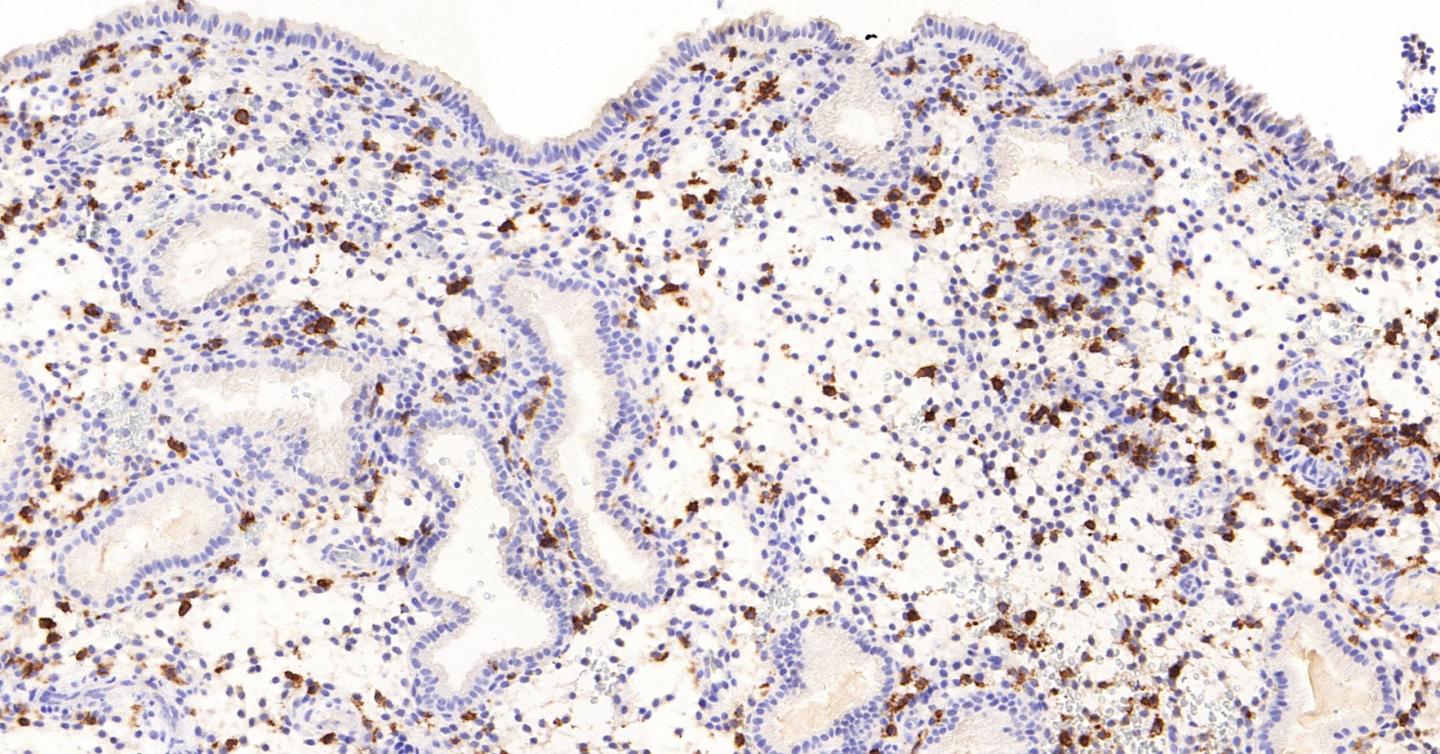

First the researchers discovered that the uterine natural killer cells remodel and refresh the lining of the womb at the time of embryo implantation. This is the first time a role for uterine natural killer cells in the lining of the womb has been identified outside of pregnancy.

In addition they discovered that this process isn't always balanced in each cycle. The natural killer cells perform the role of targeting and clearing inflammatory stressed cells, thereby making space for the implanting embryo. However sometimes not enough of these cells are cleared away and sometimes too many are targeted and removed. Excessive inflammation or insufficient clearance by uterine natural killer cells makes miscarriage more likely.

Their research is based on large amounts of experimental and observational data. They conducted an analysis of 2,111 endometrial biopsies, which is more than had ever been conducted previously. These were kindly donated by women who have attended the Implantation Research Clinic at UHCW NHS Trust. The research team examined the acutely stressed (acutely senescent) cells in the lining of the womb which generate tissue inflammation that is needed for embryo implantation. They found that the natural killer cells which are in the womb perform the important function of selectively targeting and eliminating acutely stressed cells. They perform this as the cycle progresses.

Also the researchers data suggest that acutely stressed cells in the lining of the womb are responsible for generating the elusive 'implantation signal' in the human uterus.